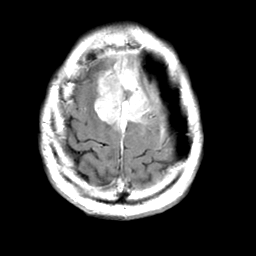

Meningioma, MR Study #2 -- Slice #18

[Home][Help][Clinical] Slice 18